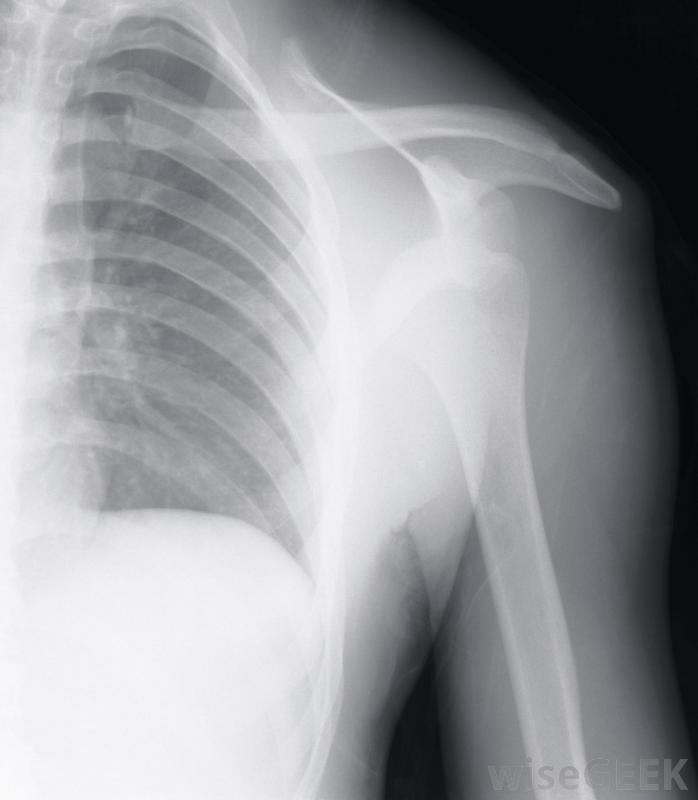

肩關節勞損是一種肩部損傷,肩部肌肉發炎會導致反復疼痛。這種勞損可能是由于體力活動時過度用力、事故中受傷或發展某種持續的健康問題引起的。在許多情況下,肩關節勞損可以用休息和藥物的結合有助于減輕痛苦,并使肩膀愈合。肩部勞損可能會導致很大的疼痛肩關節拉傷最常見的原因是肩部周圍不同形式的組織受損。肌腱和軟骨承受的壓力會導致大量炎癥,進而導致腫脹,從而對肩關節施加壓力關節本身。當這種情況發生時,移動肩膀會導致很大的疼痛,可能難以忍受。肩關節勞損的根本原因可以從X光片中發現關節炎和缺血性壞死等退行性疾病也可能是肩部勞損和疼痛的根源,關節炎會磨損軟骨,甚至會影響肩關節骨的強度。炎癥開始,使肩膀很難正常移動通常情況下,需要藥物來控制炎癥,并幫助患者獲得至少一些緩解疼痛的效果。一個包括肩部許多肌肉的解剖圖隨著缺血性壞死,肩部骨骼的血液供應中斷,這導致骨骼慢慢地饑餓和萎縮。隨著骨骼的死亡,如果沒有劇烈的疼痛,肩關節的正確旋轉是不可能的。通常,手術是唯一的解決辦法,雖然在疾病的早期階段使用藥物是有幫助的,但是診斷肩關節勞損的潛在原因至少需要進行一次身體檢查。通常,主治醫生也會要求檢查X光或磁共振成像,也被稱為核磁共振成像。這有助于確定疼痛的原因是由于過度勞累,還是有一個正在發展中的健康問題必須解決,以減輕由勞累引起的不適肩關節勞損的治療過程中可能有幾個因素。使用消炎藥是相當普遍的。根據勞損的原因,在一天中對肩部進行熱敷和冷敷可能有助于消腫和減輕一些疼痛物理治療也可能是必要的,以幫助恢復一定的運動范圍和幫助促進受損組織的愈合。在大多數情況下,手術通常被認為是最后的手段,出現缺血性壞死是一個明顯的例外體力活動期間過度用力會導致肩部勞損。